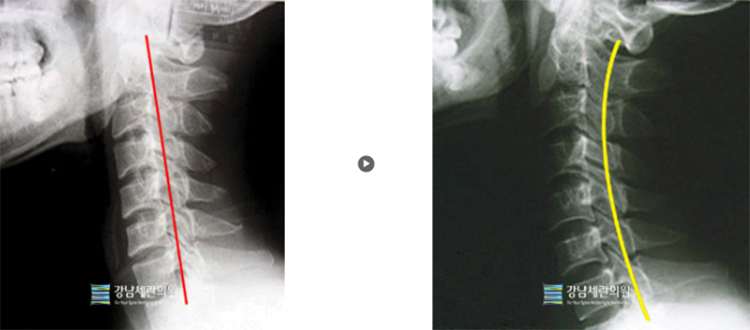

#일자목

일자목 치료 전 ▶ 일자목 30회(3개월) 치료 후